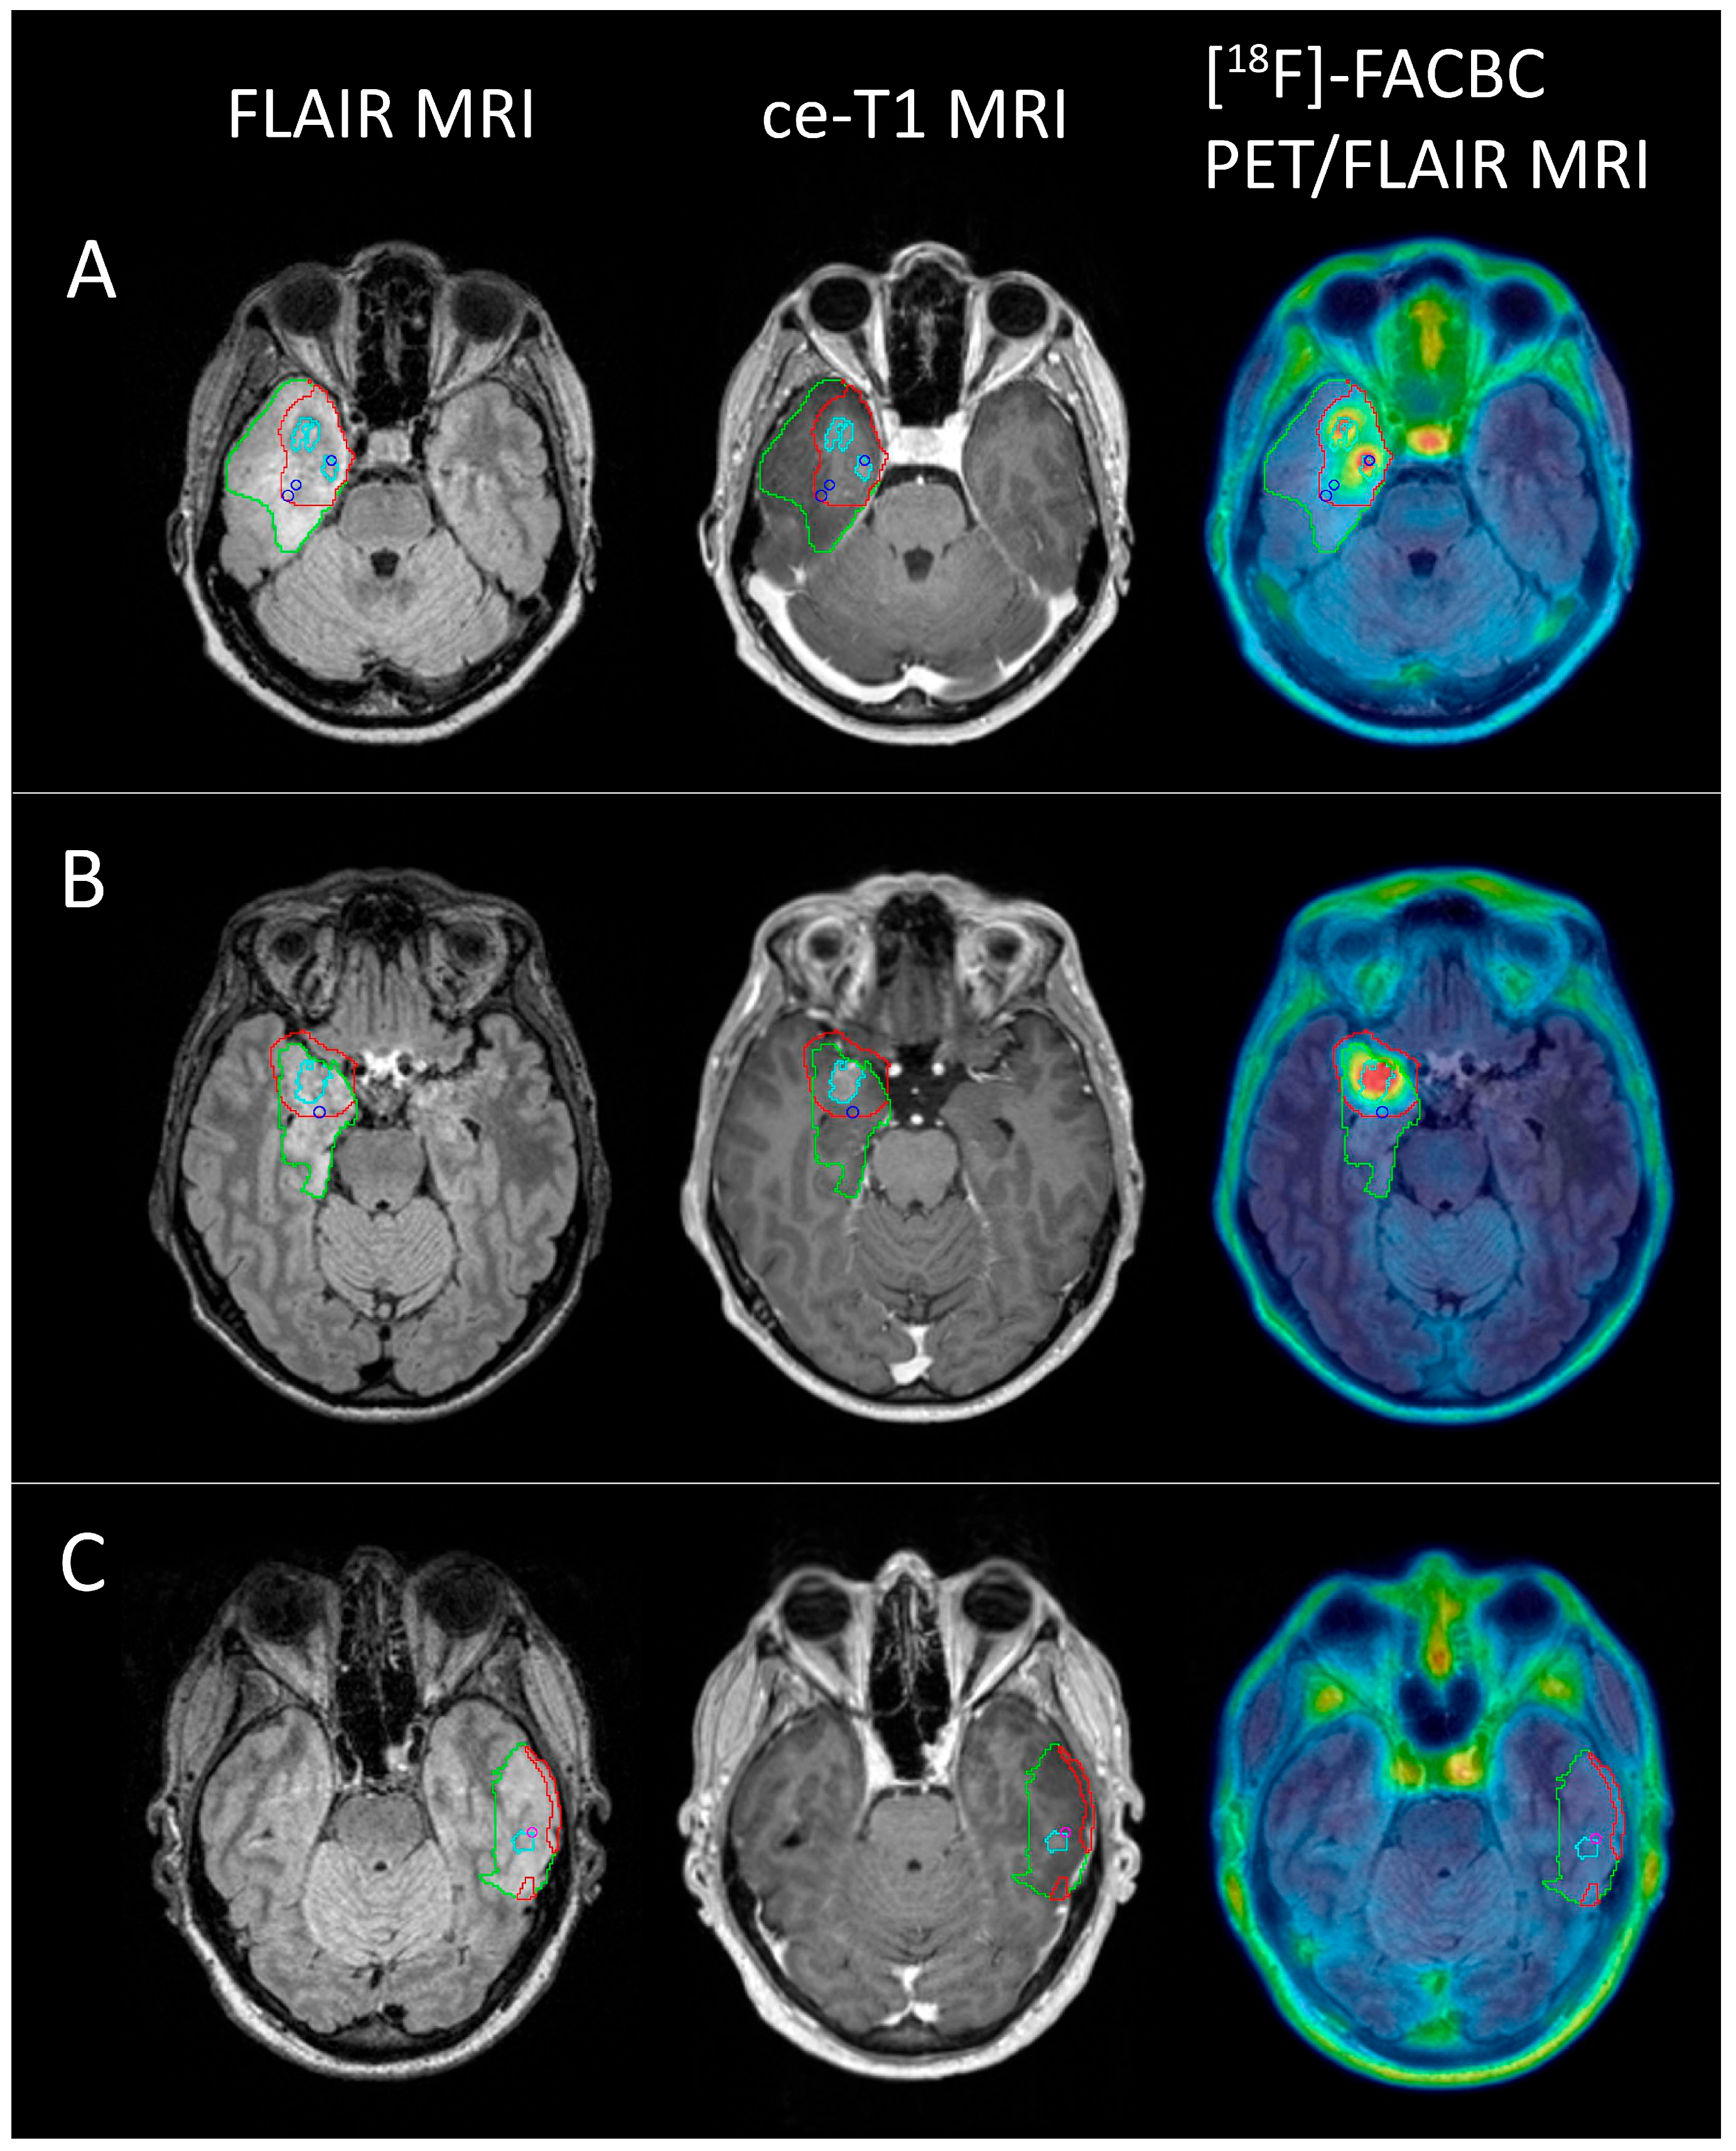

In total, 19 biopsies were sampled from the eight patients with glioblastoma, of which 16 were classified as tumor tissue and 3 as non-tumor tissue. With a TBR threshold of 2, the PET volume included 14 of the tumor-positive biopsies (87.5%), while the ce-T1 volumes included 5 (31.3%). Of the three biopsies classified as non-tumor tissue, one fell within the PET volume, while two fell within the ce-T1 volumes. Examples of PET volumes and MRI volumes for three of the patients are shown in Figure 6.

Figure 6.

FLAIR (green), PET (red), and ce-T1 (cyan) MRI volumes for 3 glioblastoma patients ((A) female, 52; (B) male, 46; (C) female, 50) shown on FLAIR MRI, ce-T1 MRI, and PET/FLAIR images. Blue circles show biopsy coordinates classified as HGG (A,B), while the pink circle shows biopsy coordinates classified as non-tumor tissue (C). Two HGG biopsies from (A) and one from (B) did not show contrast enhancement, but were positive for [18F]-FACBC PET at a threshold of TBR = 2. One non-tumor biopsy from C was ce-T1 positive, but did not have [18F]-FACBC uptake.